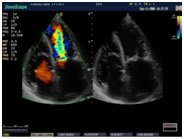

В Медицинском центре «АКВА МЕД МАРИН» проводится УЗИ-диагностика на новейшем ультразвуковом диагностическом сканере Экспертного класса SonoScape S40Exp, в том числе и УЗИ детям с применением специальных детских датчиков. Цветной допплер помогает точной диагностике патологии сосудов и сердца у детей.

Компания SonoScape уделила особое внимание допплеровским режимам и является экспертом в своем классе, что позволяет с легкостью, но в то же время с уникальной точностью проводить исследования с постановкой наиболее точного диагноза.

Ультразвуковые исследования, доплеровское сканирование сосудов в Медицинском центре «АКВА МЕД МАРИН» выполняется при помощи аппарата SonoScape S40Exp (экспертного класса, который оснащен множеством новейших функций, многократно улучшающих качество и информативность УЗИ-исследования).